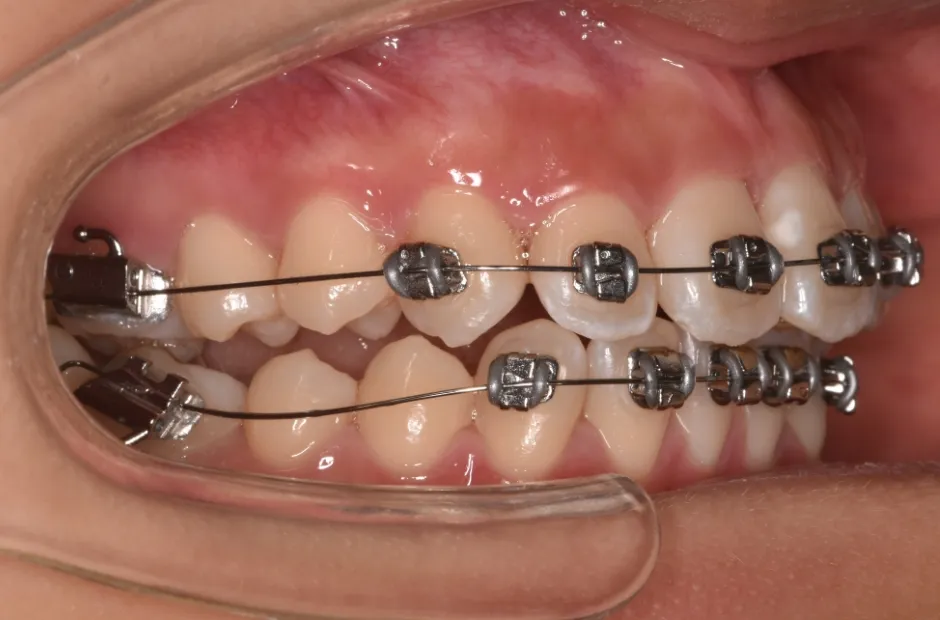

治療症例

ブラケット矯正

前歯部反対咬合

| 診断名・主訴 | 前歯部反対咬合 |

|---|---|

| 年齢・性別 | 14歳・男性 |

| 治療期間・回数 | 1年2か月 |

| 治療に用いた主な装置 | ブラケット矯正 |

| 抜歯部位 | なし |

| 治療費 | 60万円(税抜) |

| リスク・副作用 | 装置による違和感・疼痛・歯肉退縮・歯根吸収・虫歯のリスクなど |

治療前

治療中